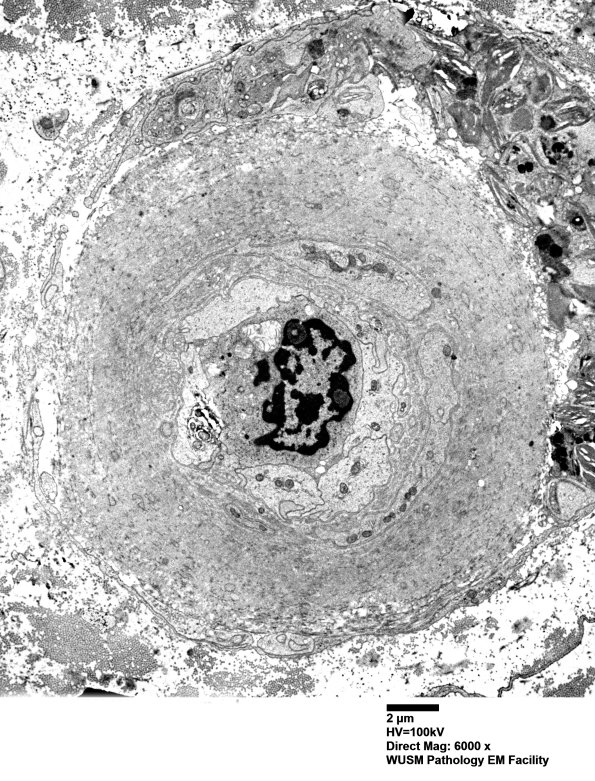

5C1-3 Many endoneurial blood vessels show significant mural thickening consisting largely of collagen but including some fragments of basal lamina. There is an appearance of occlusion or near-occlusion of vascular lumens with plump endothelial cells. There are no collections of neoplastic cells. (electron micrographs)